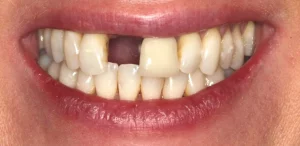

This lady was very upset after a dumbbell hit her mouth in the gym and knocked the front tooth out.

A temporary bridge was made to avoid her having to wear a temporary denture during the teatment, which is less comfortable.

A single implant with bone grafting was placed.

Once the implant was bedded into the bone, a new porcelain crown was fitted on the implant, and a new crown was placed on the adjacent tooth to match in better.